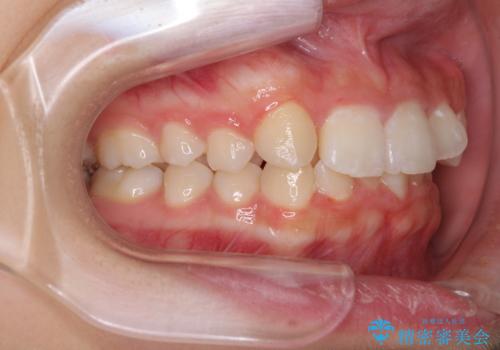

- 八重歯やデコボコをインビザラインで治療したいとのことで来院された患者様です。

インビザライン単体で治療を行うには叢生が強いと判断されたため、事前にワイヤー装置で抜歯矯正を行い、ある程度改善してからインビザラインにて仕上げていくこととしました。